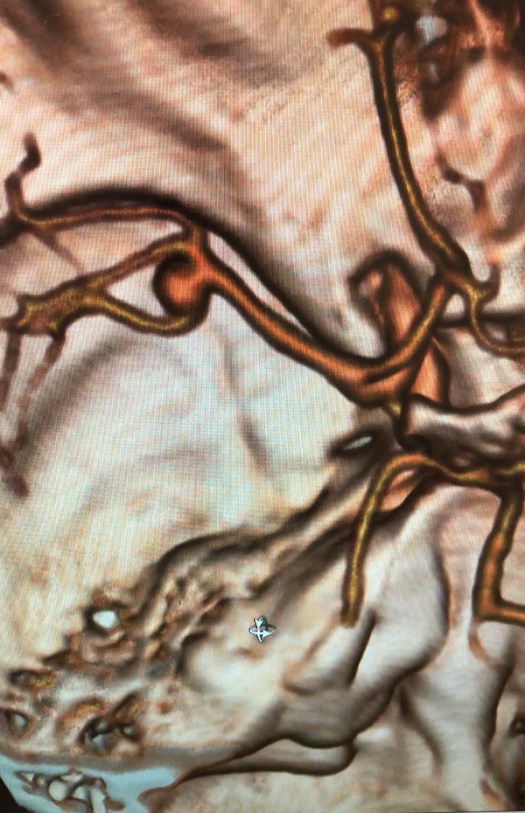

Clipping di aneurisma complesso M1-M2 di sinistra – ricostruzione biforcazione arteria cerebrale media